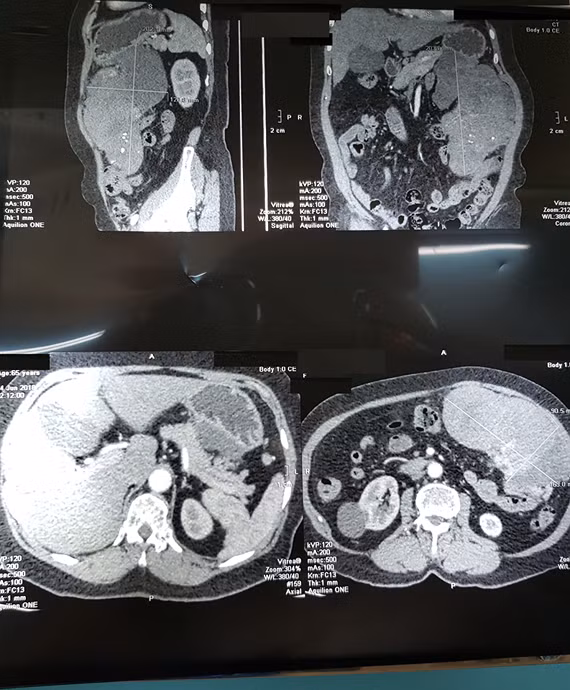

| Hình chụp cắt lớp khối u của bệnh nhân N.T.L. |

Kết quả siêu âm cũng cho thấy một khối u kích thước lớn, chưa rõ bản chất. Bên cạnh đó, kết quả CT scan khảo sát vùng bụng phát hiện khối u mô đệm thành dạ dày, choán chỗ toàn bộ vùng hạ sườn trái, có đường kính lớn nhất lên tới 20 cm. Ngay lập tức bà L. được chuyển đến Bệnh viện Bình Dân để nội soi dạ dày-tá tràng, kết quả cho thấy một khối u dưới niêm mạc dạ dày dạng u mô đệm đường tiêu hóa (GIST-Gastrointestinal Stromal Tumor).